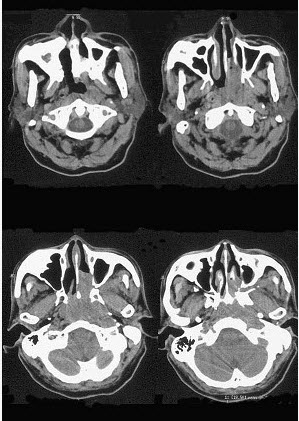

男,64岁,间断性流鼻血一年余,近1个月加重,CT如图所示,最可能的诊断为()。

A、鼻咽部腺样体增生

B、鼻咽纤维血管瘤

C、鼻咽部恶性淋巴瘤

D、鼻咽部淋巴组织增生

E、鼻咽癌

E